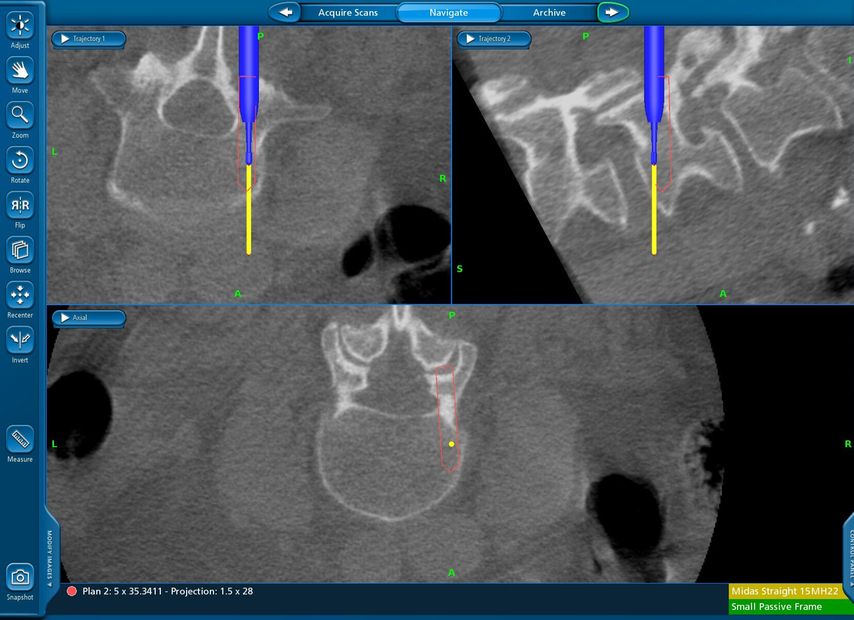

Beispiel für die Implantation zervikaler Pedikelschrauben. In diesem Fall kam es bei einem 61-jährigen Patienten 10 Jahre nach anteriorer zervikaler Diskektomie und Fusion (ACDF) C4/5 und ventraler Verplattung C4–6 zu einer Ankylosierung auch von C6/7. Nach Sturz kam es zu einer Fraktur bei C6/7 mit begleitender Bogenfraktur und auch Beteiligung der dorsalen Ligamenta (Abb. 1 und 2). Klinisch bestanden ausgeprägte Nackenschmerzen und kein neurologisches Defizit. Es wurde die Indikation der dorsalen Verschraubung von C4 auf Th1 gestellt. Intraoperativ wurde routinemäßig zusätzlich eine kleine Referenzschraube in einer Lamina – entfernt von der Dornfortsatz-Referenzklemme für die Navigation – gesetzt. Mit dieser konnte intraoperativ die Genauigkeit der Navigation exakt überprüft werden (Abb. 4 und 5). Mittels navigierter High-Speed-Fräse wurden die Schraubenkanäle vorgebohrt (Abb. 6), im Anschluss wurde der Bohrkanal ausgetastet und die Schrauben wurden implantiert. Abbildung 7 zeigt eine Röntgenkontrolle 3 Monate postoperativ.

Abb. 4: Screenshot der Navigationssoftware intraoperativ (Stealth Station S7). Es erfolgt die intraoperative Verifizierung der Navigationsgenauigkeit mittels kleiner Schraube in der Lamina, positioniert idealerweise entfernt von der Dornfortsatz-Referenzklemme. Die navigierte Fräse wird im Situs exakt auf die Schraubenmitte gerichtet, und die Navigation bestätigt die Genauigkeit | |